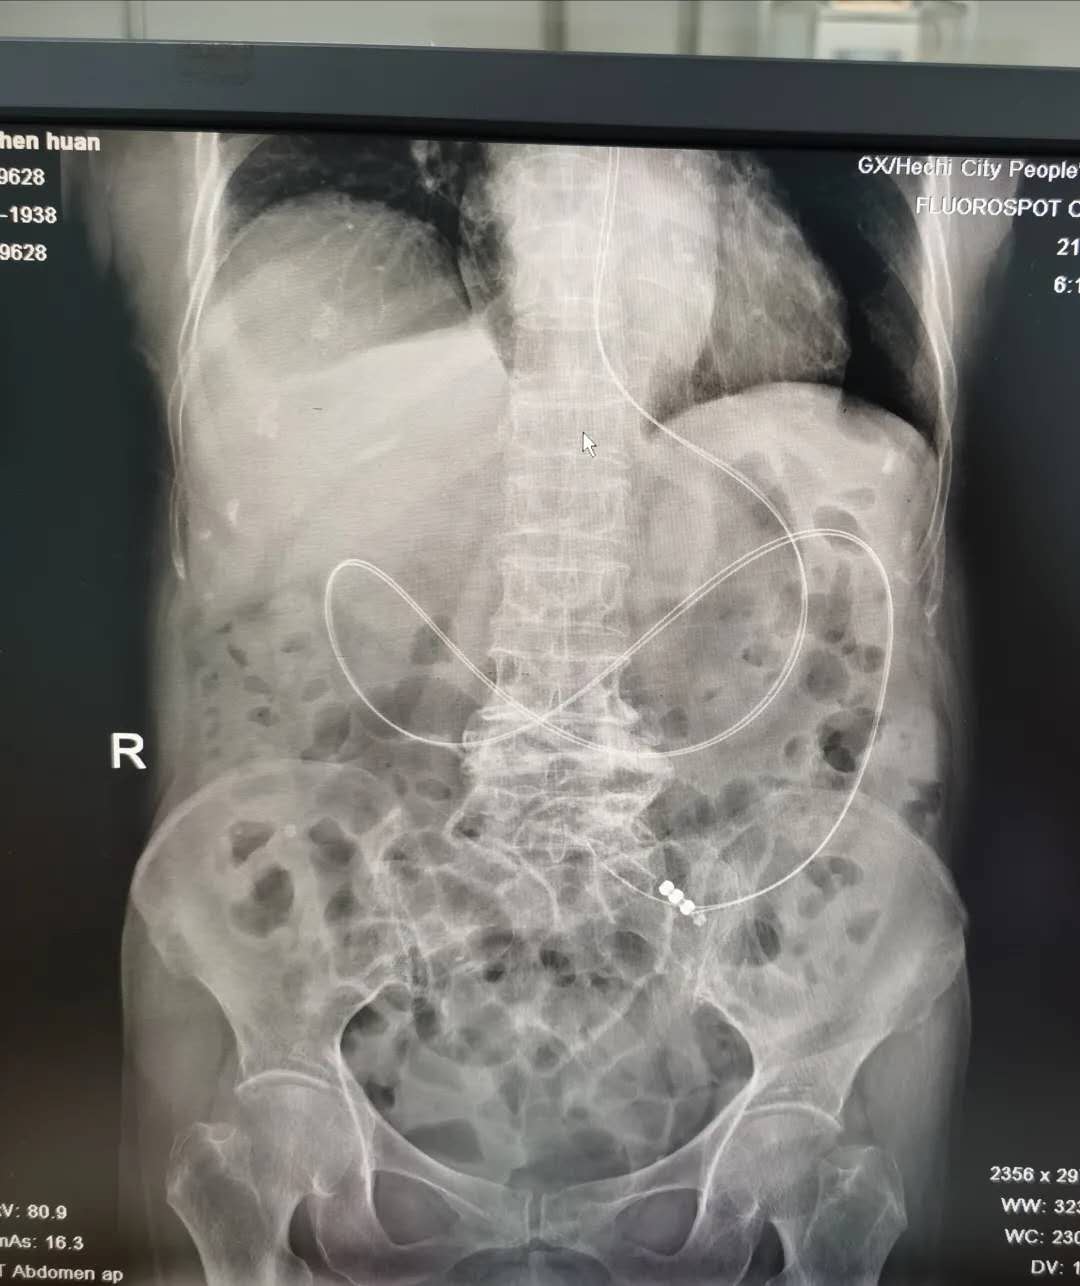

9月21日下午,超声科韦荣文主任、神经外科盘丽华护士长共同为患者行超声引导下鼻空肠管置入术,由于空肠管较长加上途经的解剖结构复杂,曲折,空肠管能顺利穿过幽门是置管的关键和难点,但最后经过两人默契的配合,顺利地将空肠管经鼻腔、胃到达十二指肠,成功置入患者空肠内,手术过程中患者无呛咳、无胸闷气促等现象,置管手术顺利完成。术后,经过腹部平片检查,结果显示该管道完整到达空肠腔内。置入后患者无不良反应,进食后无发生呕吐现象。

图为置管术后腹部平面结果